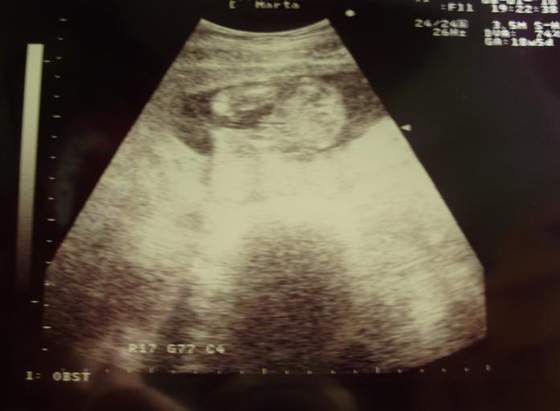

A to świeżutkie zdjęcia mojego "zagadkowego" nadal dzidziusia :-)

na tym pierwszym zdjęciu, myślałam,że to siusiak, ale to jest pępowina :-)![]()